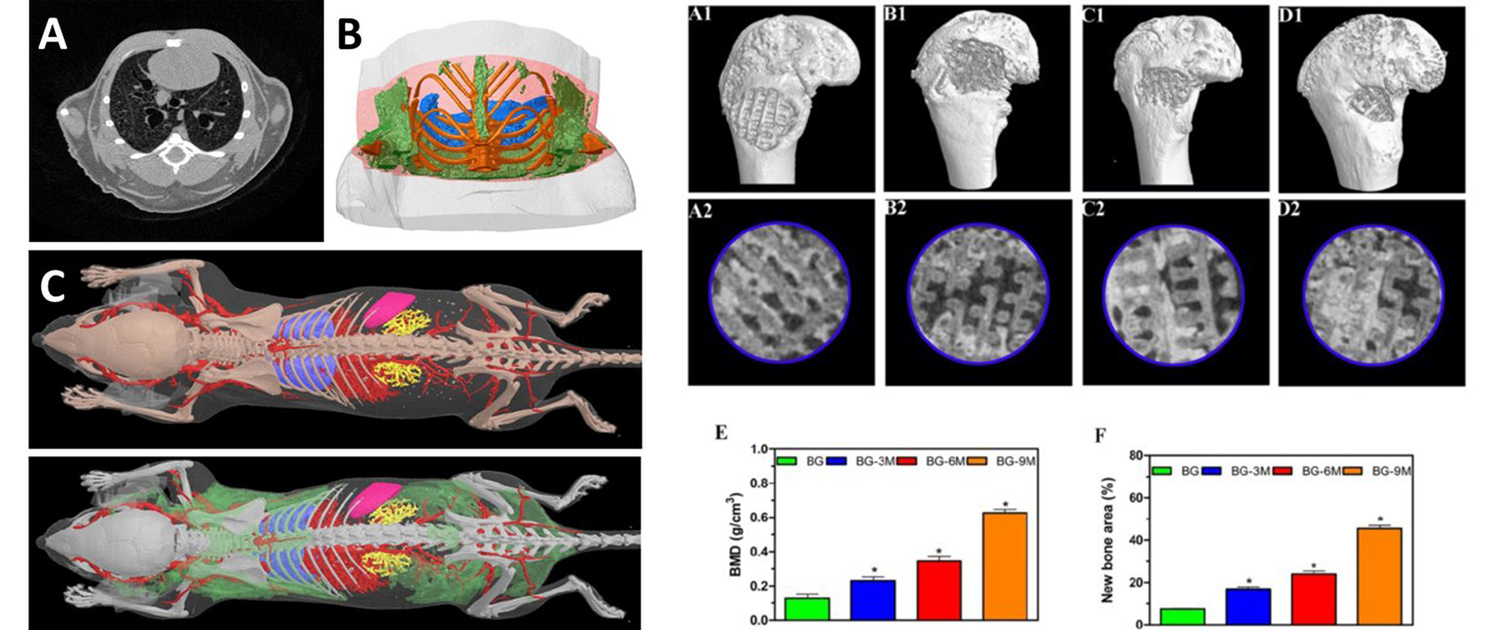

Image analysis is a critical component of clinical and preclinical imaging research, providing a means of quantifying and interpreting the data generated by imaging modalities such as PET, SPECT, and CT. In clinical imaging, image analysis is used to aid in diagnosis and treatment planning. For example, in oncology, image analysis can be used to assess the response to chemotherapy and radiation therapy, providing a means of monitoring the effectiveness of treatment and making adjustments as necessary.

In cardiology, image analysis can be used to evaluate blood flow and cardiac function, enabling the diagnosis and treatment of heart disease. In preclinical imaging research, image analysis plays a crucial role in the development of new treatments and therapies. Image analysis algorithms can be used to quantify the effects of drug treatments or surgical procedures on biological processes such as blood flow and metabolic activity. By providing a means of objectively assessing treatment efficacy, image analysis helps to optimize treatment protocols and improve patient outcomes.

The same image analysis techniques can be applied to both clinical and preclinical images, allowing for a seamless transition between research modalities. Moreover, image analysis has additional applications in clinical research, beyond the evaluation of disease progression or response to therapy. For example, image analysis can be used for radiation treatment planning to optimize the radiation dose and minimize side effects.

Image analysis can also be used to evaluate the efficacy of medical devices or surgical procedures. Additionally, image analysis can be used in radiomics, which involves the high-throughput extraction of large amounts of data from medical images, allowing for the identification of imaging biomarkers that can help in patient diagnosis and prognosis. Overall, image analysis is a powerful tool in both preclinical and clinical research, with a wide range of applications beyond disease evaluation.

At our company, we provide a wide range of image analysis services for both preclinical and clinical imaging research. Our team of experts has extensive experience in conducting image analysis for various modalities, including PET, SPECT, CT, and optical imaging. We offer a comprehensive set of services, such as image registration, segmentation, quantification, and statistical analysis. We understand the importance of accurate and precise image analysis in the success of research projects, and we use state-of-the-art software and techniques to deliver reliable and reproducible results.